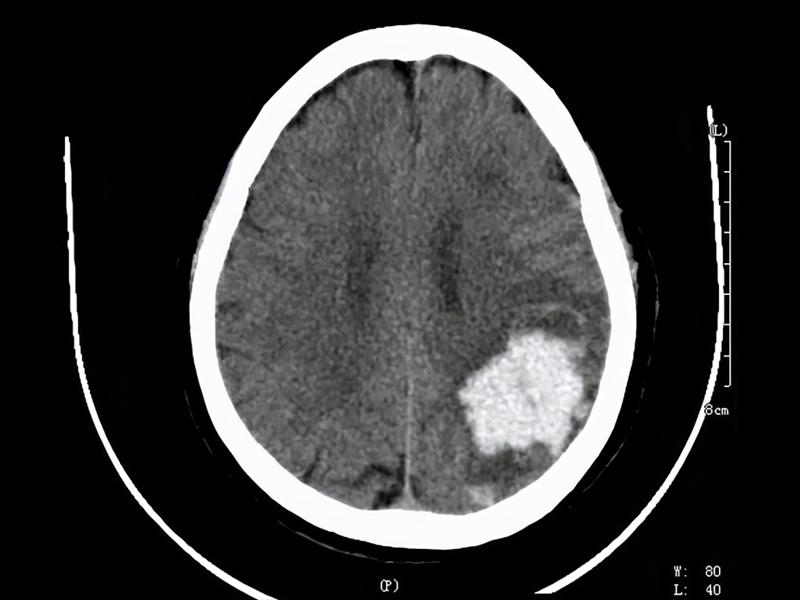

腦幹出血是神經系統的重症,疾病死亡率高。腦幹出血量在 15ml 以下,死亡率約 17.1% 左右;出血量高於 15ml 以上,死亡率 81.8% 左右;若超過20ml死亡率更高。

高血壓動脈硬化是腦幹出血的主要病因,腦幹出血是因高血壓導致基底動脈中央之破裂引起。在數秒到數分鐘內患者就會昏迷、四肢癱、針尖般瞳孔,數小時內會死亡。

據報道,這名程序員吳先生從事技術工作,月薪高達 3 萬元人民幣,但每天的工作時間從早上 7 點持續到凌晨 1 至 2 點,長期處於極度疲勞狀態。今年年初,他因腦幹出血 5 毫升陷入昏迷,昏迷長達 15 天,在 ICU 搶救 28 天後才逐漸恢復意識。隨後,他又轉入康復醫院進行 70 多天的治療,目前已恢復約 70% 的身體功能,但仍無法完全康復。

吳先生還特別提醒大眾,若經常熬夜且出現手指手掌麻木的情況,應立即就醫。「三天是黃金時間,否則可能導致腦溢血、半身不遂,甚至無法手術治療,只能靠養護慢慢恢復。」